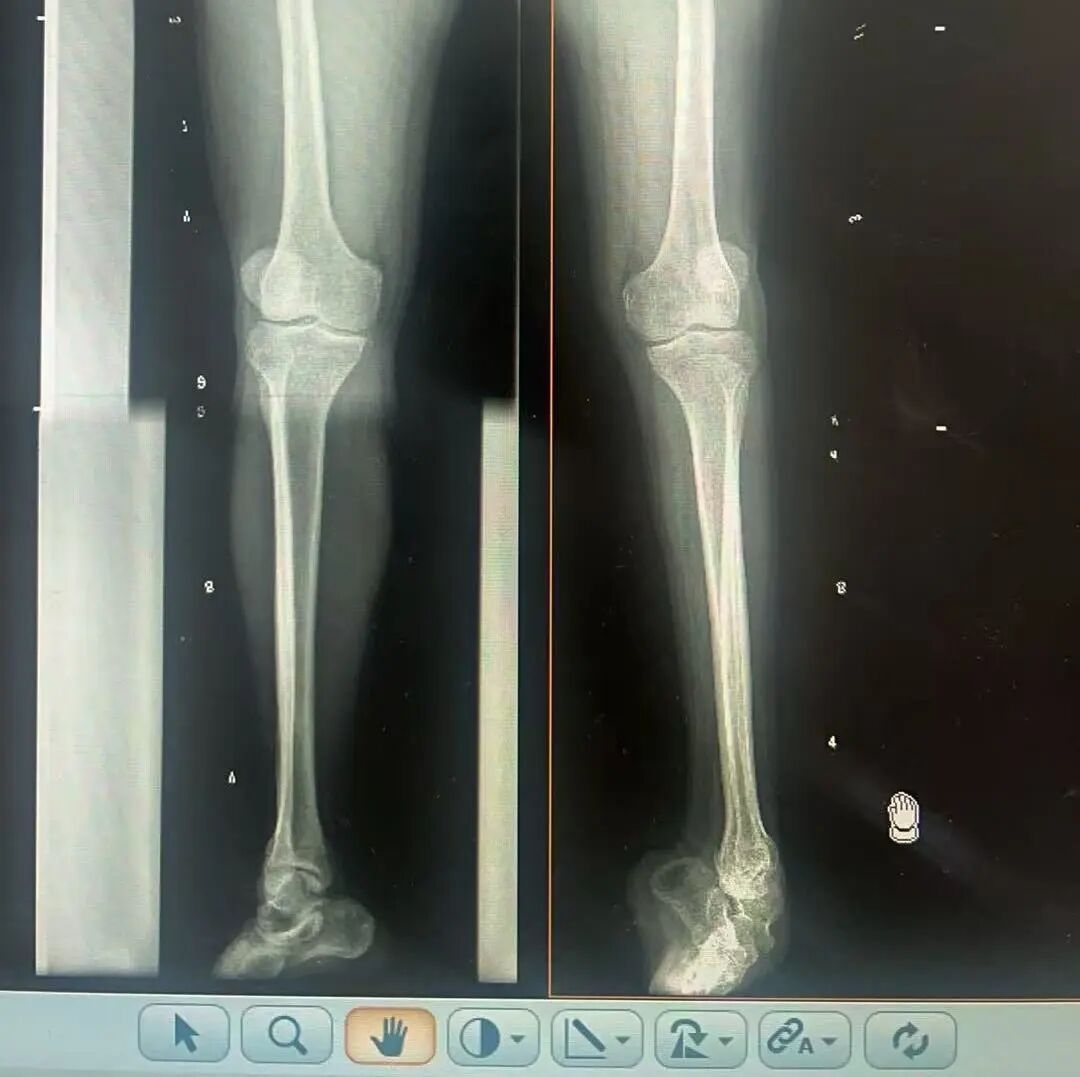

術(shù)前X光片 VS 術(shù)后治療效果

骨科隨即為陽先生進(jìn)行了全面的檢查。診斷明確而復(fù)雜:陽先生患有脊髓灰質(zhì)炎后遺癥、左踝馬蹄內(nèi)翻足、骨盆傾斜……面對(duì)這張沉甸甸的診斷書,由肢體功能重建顯微修復(fù)學(xué)科組長鄭群龍所帶領(lǐng)的醫(yī)療團(tuán)隊(duì)沒有畏懼,“這是一個(gè)家庭38年的堅(jiān)守與期盼,我們必須全力以赴”

針對(duì)陽先生的復(fù)雜情況,鄭群龍醫(yī)師團(tuán)隊(duì)制定了詳盡的手術(shù)方案:左踝關(guān)節(jié)融合+馬蹄足畸形矯正+跟腱延長+外固定架固定術(shù)。手術(shù)的核心,正是伊里扎洛夫技術(shù)。這項(xiàng)技術(shù)如同精密的“時(shí)空建筑學(xué)”,通過微創(chuàng)安裝環(huán)形外固定架,前足-后足安裝鋼環(huán),再將足的鋼環(huán)與脛骨的固定鋼環(huán)在踝關(guān)節(jié)前、后、左、右用帶關(guān)節(jié)的螺紋桿連接,由此構(gòu)建成一個(gè)能體外牽拉調(diào)控的三維立體構(gòu)型,在術(shù)后進(jìn)行精準(zhǔn)、緩慢的調(diào)整,一寸一寸逐步將畸形的骨骼、軟組織恢復(fù)到正常位置。

9月1日,在全麻狀態(tài)下,陽先生接受了伊里扎洛夫外固定架安裝術(shù)。鄭群龍團(tuán)隊(duì)在陽先生左足足踝部植入克氏針及半針,安裝外固定架,通過支架的機(jī)械結(jié)構(gòu)對(duì)馬蹄內(nèi)翻畸形進(jìn)行緩慢、持續(xù)的牽拉矯正。術(shù)后,鄭群龍團(tuán)隊(duì)反復(fù)指導(dǎo)訓(xùn)練陽先生父子進(jìn)行外固定架的日常調(diào)試,按照預(yù)定計(jì)劃每日調(diào)整螺桿,逐漸糾正足部畸形,并配合專業(yè)的康復(fù)訓(xùn)練,包括踝關(guān)節(jié)主動(dòng)及被動(dòng)活動(dòng)、下肢肌力訓(xùn)練等項(xiàng)目促進(jìn)陽先生腿部肢體功能恢復(fù),預(yù)防肌肉萎縮及關(guān)節(jié)僵硬。